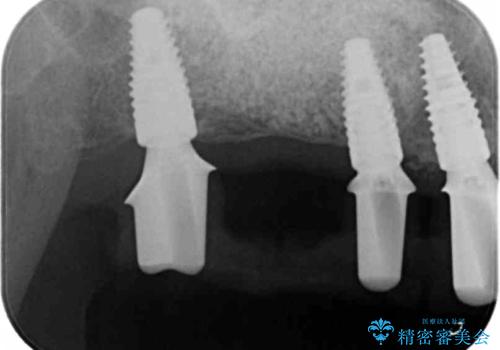

残すことのできない歯を抜去したのち、骨を造成し安定した環境下で長期的な予後を期待できるインプラント治療を計画します。

- 275万円(インプラント×5・チタンカスタムアバットメント×5・ジルコニアクラウン×7・仮歯×7)費用は治療当時の料金となります

奥歯を多数失い全く噛めない期間があり、困り果てて来院されましたが、インプラント治療をおこなったことでしっかりと噛めることができるようになりまた食事を楽しめるようになったと大変喜んでいただくことができました。